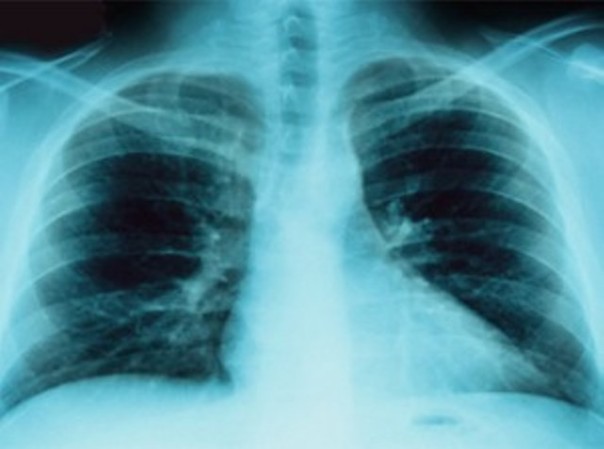

Tumori, quello al polmone seconda causa di morte nelle donne toscane

FIRENZE – A causa della diffusione sempre più ampia del tabagismo, il tumore al polmone è diventato per le donne toscane la seconda causa di morte dopo quello alla mammella, superando per incidenza quello al colon. E’ quanto rilevato dagli epidemiologi dell’Istituto per lo studio e la prevenzione oncologica (Ispo). Negli uomini il tumore al polmone resta la prima causa di decesso, anche se in diminuzione grazie a comportamenti virtuosi tra i quali proprio la riduzione dell’abitudine al fumo.